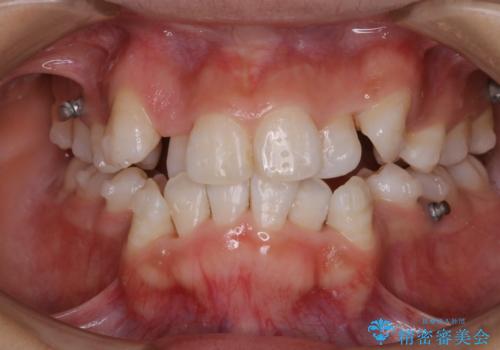

表のワイヤー矯正治療中にPMTCで綺麗に

担当医 歯科衛生士